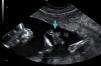

Caso clínicoGestante de 29 años, con el antecedente de legrado obstétrico por aborto espontáneo de primer trimestre, que acude a la Consulta de Diagnóstico prenatal para realizar el cribado de aneuploidías fetales, con una edad gestacional de 12 semanas. En la ecografía se visualiza un embrión acorde a la edad gestacional, con latido cardiaco positivo y la presencia de una estructura hiperecogénica, sin flujos vasculares en su interior, que surge de la pared amniótica y afecta al miembro inferior distal derecho, presentando una movilidad espasmódica del tercio medio inferior de la pierna, con pequeños movimientos de flexoextensión, pero con una movilidad reducida por la brida. Dicha brida se adhiere además a la cara anterior abdominal y a uno de los brazos (figs. 1-5). Se repite la ecografía a la semana, comprobando los mismos hallazgos y ante el mal pronóstico la paciente decide interrumpir la gestación.